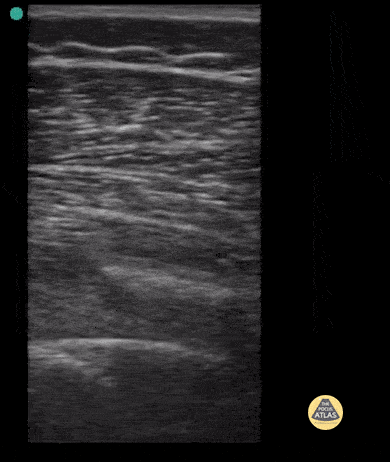

Long axis view of 9 year old male with spiral femur fracture with displacement. Note cortical disruption seen at about 5-6 cm in both long and short axis. Case Series 2 of 2 Contributor: Antonio Riera, MD